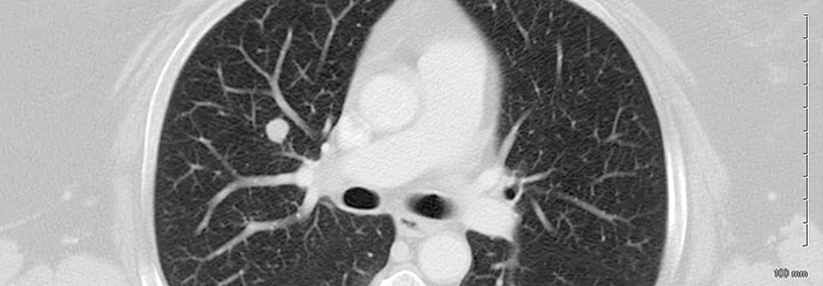

Die Phase-2-Studie MEGAMOST untersucht zielgerichtete Therapien bei fortgeschrittenen Tumoren, einschließlich Liposarkomen. Die Phase-2-Studie MEGAMOST untersucht zielgerichtete Therapien bei fortgeschrittenen Tumoren, einschließlich Liposarkomen. © ibreakstock – stock.adobe.com